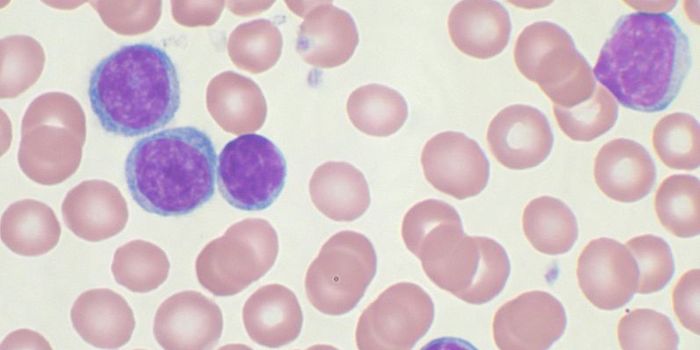

AUG 22, 2014Genetics & GenomicsEpigenetics has a large say in blood formation.

Blood stem cells have the potential to turn into any type of ... -